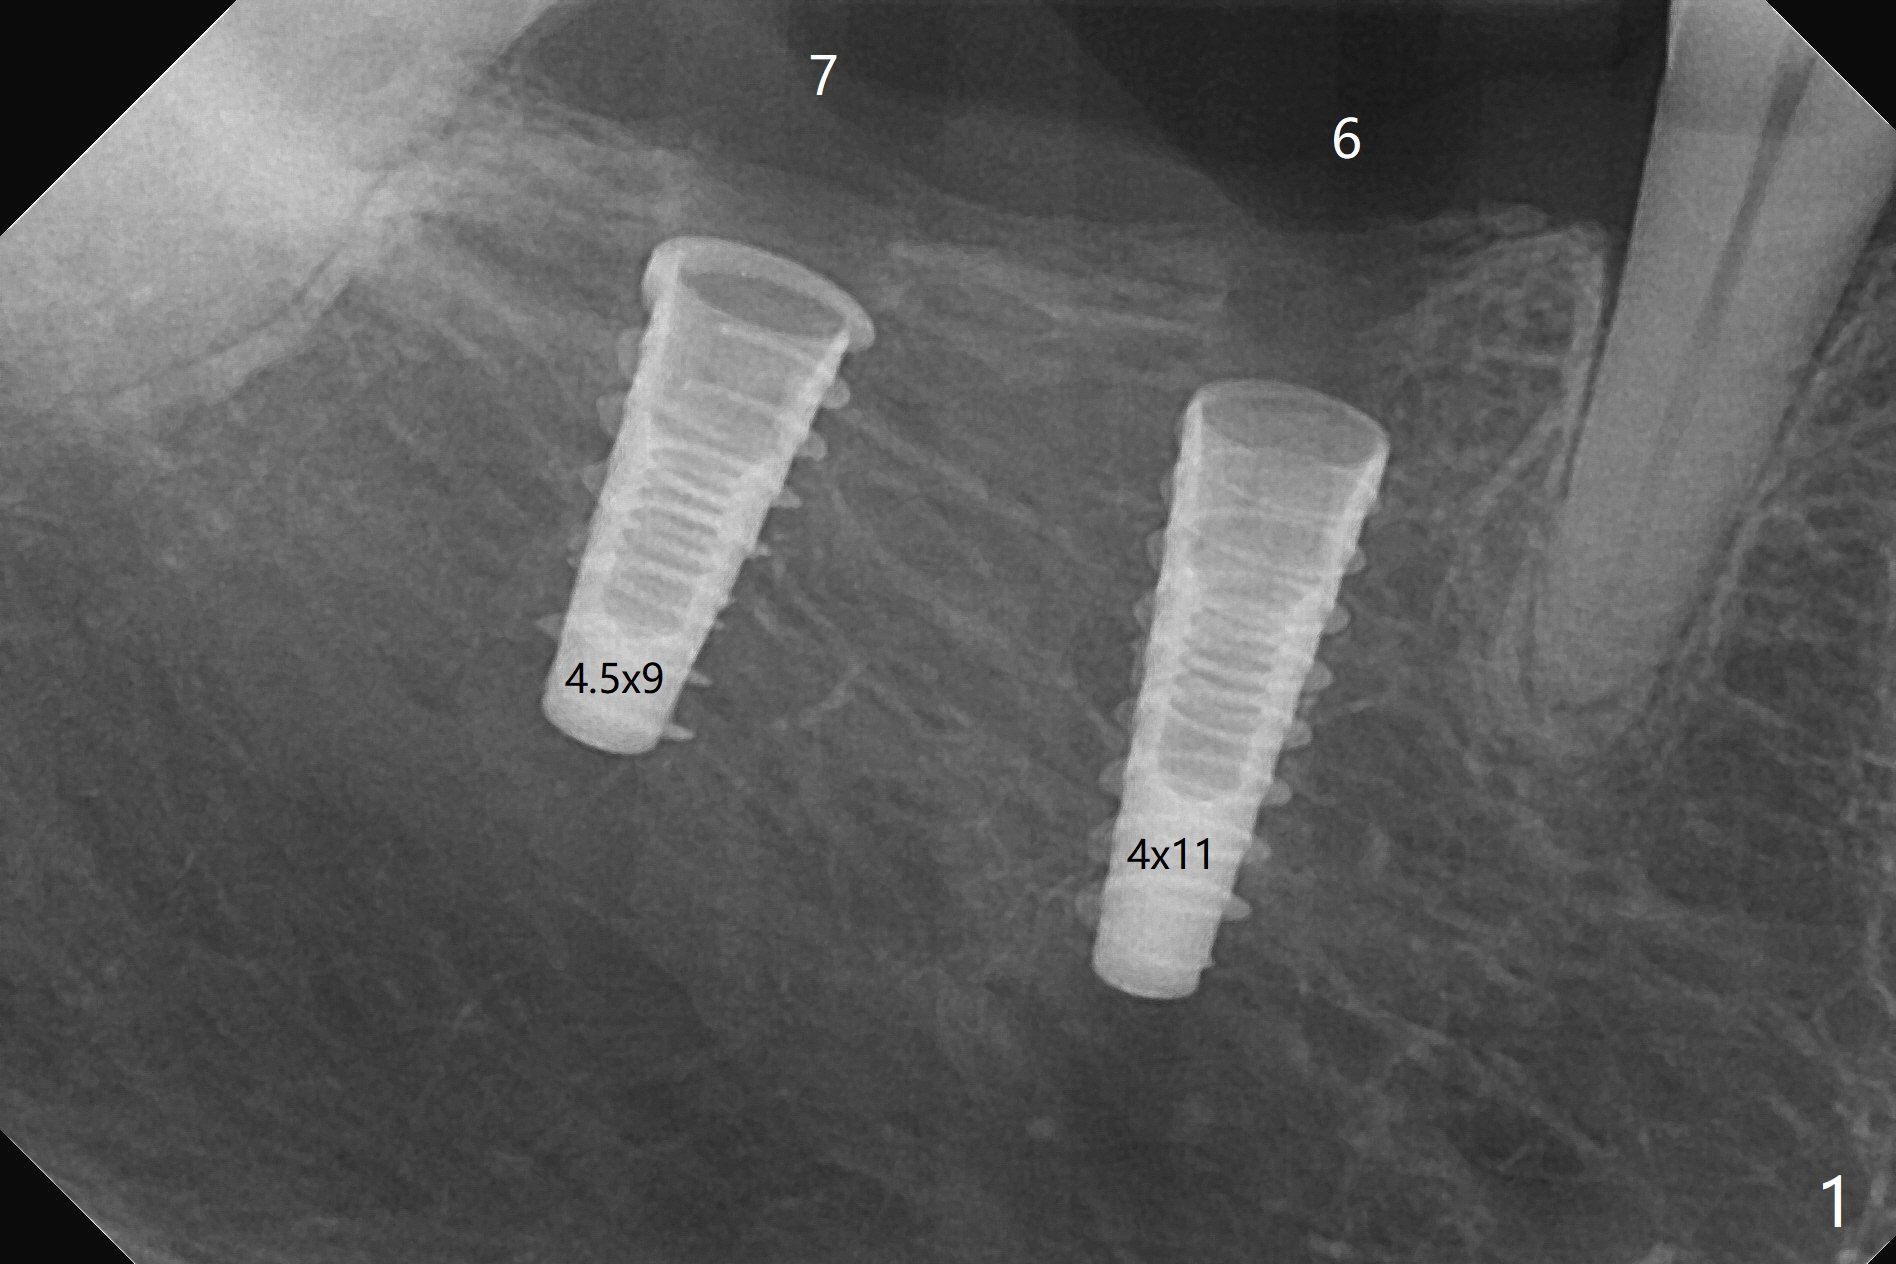

害怕病人局麻药很慢起效,术中身体会动,术中决定减小右下6,7植体直径0.5毫米(与导板设计相比),一旦植体越过牙槽嵴顶骨皮质,稳定性突然减低(图一)。尽管扭力10-15Ncm,为了避免二期手术,放置愈合基台(图二),6基台没有就位(箭头),因为植体种太深了,牙槽骨阻挡(*)基台就位。当取出6基台时,植体一起旋出,重新植入时,就没有种那么深(图三:箭头,与图一,二对比)。由于扭力低,只好放置愈合帽,骨粉(*),GEM Cap(6-9月胶原膜)和牙周胶水。由于导板设计缘故,左上5拔除,种植后,才开始左上3一段式植体植入(图四),5也植入太深(图五),必须放置最小直径最长袖(cuff)的基台(图六),今后导板即刻植牙先不要到达设计深度。术后一周CT显示尖牙植体位于牙槽骨内(图七 (>:腭侧牙槽嵴))。Bone graft fills in the buccal apical defect at #13 one week postop (Fig.8 <). 术后两个月左上3临时牙冠折裂,5松动(图九,十),后者取出衬里,软组织愈合。术后8个月左上3,5取模,右下6 uncover,愈合帽表面覆盖骨质,把7号牙愈合基台放到6号牙上,而7号牙放置4.5x4(4)毫米修复基台,固定牙周敷料,这样6号牙伤口不必缝合。术后8.5个月右下6放置4.5x7.5(4)毫米基台,发现7基台没有就位(图十一:箭头),通过旋转7 基台,终于就位(图十二),螺丝往下移位(与图十一:横线对比),但是基台边缘太低,不利于取模。改用5.5x4(5)毫米UF基台,临床上不能就位,局麻使用5.5毫米Profile Drill后,才能就位(图十三),螺丝下端超越最低螺沟(横线)。